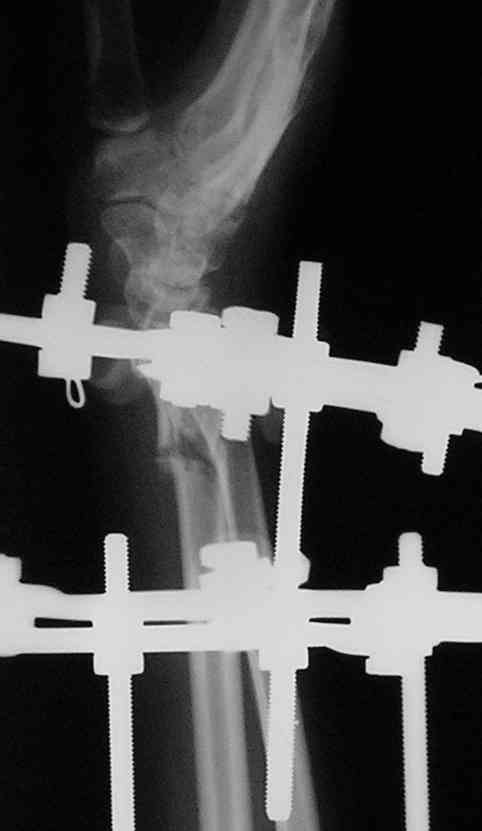

Спице-стержневой аппарат с компактотомией лучевой кости, костная пластика локтевой с удалением пластины. Не комфортно, но больше шансов на благоприятный исход. Заканчиваю лечение с похожей деформацией лучевой кости.

Виктор, спасибо за высланные фото и Ргграммы.

У больного/ой кроме перелома лучевой кости и шиловидного отростка локтевой, разрыв дистального радиоульнарного сочленения, перелом ладьевидной кости и ладьевидно-полулунная диссоциация.

Если позволите свое мнение, не стал бы лечить аппаратом эту травму, перелом луча не консолидировался: открытая репозиция+ костная пластика+ пластина, синтез ладьевидной кости, по возможности шов ладьевидно полулунной связки,

если восстановить связку не представляется возможным, фиксация 2 спицами.